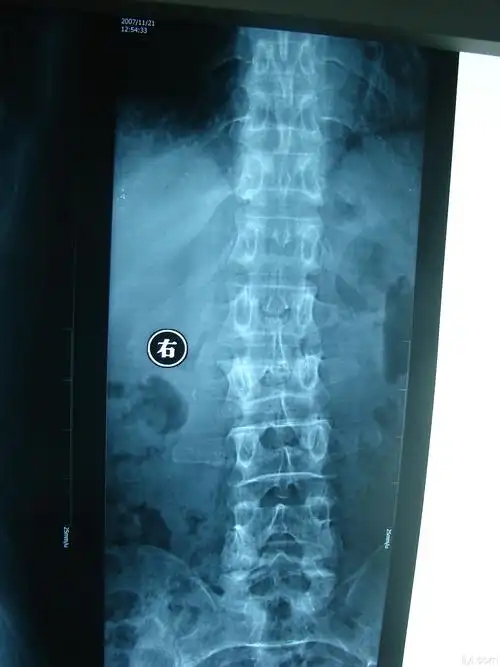

患者,女,55岁 第二腰椎爆裂性骨折